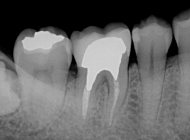

モノマー成分に含まれる4-METAが歯質に浸透して拡散し、良質な樹脂含浸層とレジンタグを形成します。